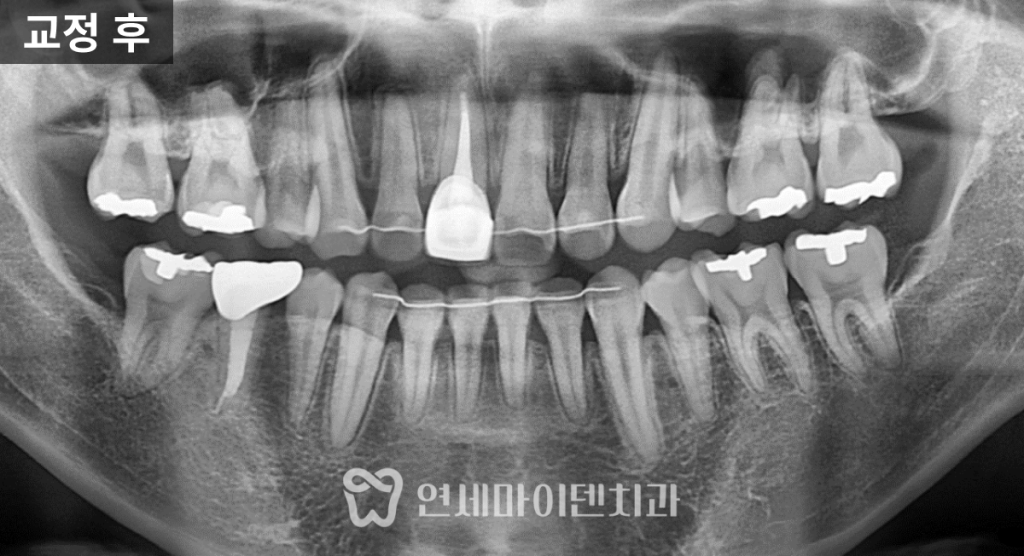

염증과 불완전한 신경치료가 있었던 치아를 발치하고

사랑니까지 함께 정리한 뒤 교정을 진행했습니다.

치료 종료 시점에서는 뿌리 흡수 없이

안정적인 상태로 마무리되었습니다.

치료 완료 (2년 9개월)

최종적으로 모든 발치 공간이 닫히고

- 발치 부위는 보철 치료를 통해 대칭성 확보

- 어금니 교합 안정적으로 회복